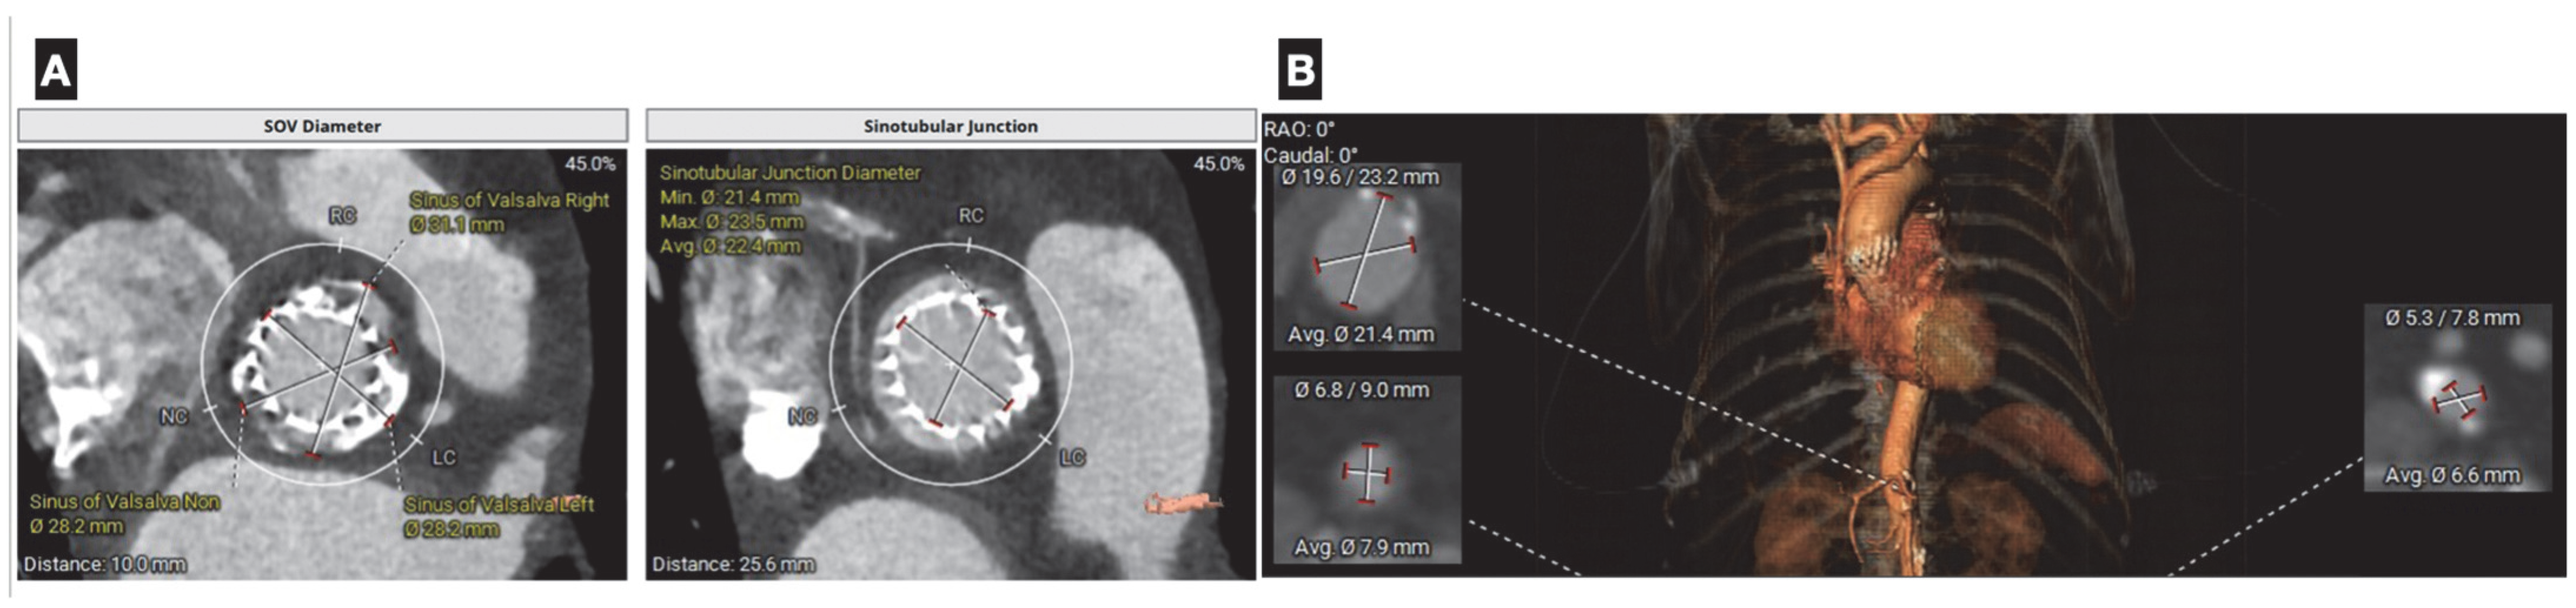

In the assessment of aortic stenosis, when there is uncertainty about the severity with echocardiography or when dobutamine stress echocardiography is inconclusive or contraindicated, non-contrast cardiac CT calcium scoring can be used to help confirm the severity of aortic stenosis (AS), as it offers a load-independent anatomical assessment. In men, calcium scores more than 2000 Agatston units, and more than 1200 in women, generally indicate severe aortic stenosis (AS) [46] (Figure 5).

Furthermore, direct measurement of the aortic valve coaptation area defect can be achieved through planimetry at the leaflet tips. This technique also enables precise assessment of aortic regurgitation by examining valve closure during diastole. Prior to transcatheter valvular aortic replacement (TAVR), CCTA can offer precise measurements of not only the aortic annulus but of the entire aortic root and offers essential information in the assessment of vascular accesses [47] (Figure 6). The clinical impact of CT-based planning is supported by real-world evidence: Mylotte et al. reported that CT analysis frequently resulted in larger annular measurements than transesophageal echocardiography (TEE) alone, and that adherence to CT-based oversizing criteria was independently associated with a 21% lower incidence of paravalvular leak compared with TEE sizing (14% vs. 35%; p = 0.003) [48]. Similarly, in a prospective study of 266 patients, CT-based prosthesis sizing significantly reduced paravalvular leak rates (5.3% vs. 12.8%; p = 0.032) and in-hospital mortality (3.8% vs. 11.3%; p = 0.02) compared with sizing based on echocardiography and angiography [49]. Post-TAVR, cardiac CT is valuable in the evaluation of suspected prosthetic valve thrombosis, endocarditis, or structural deterioration, with characteristic findings such as hypoattenuated leaflet thickening (HALT) and reduced leaflet motion (HAM) providing important diagnostic information for targeted management. Likewise, Yin Ge et al. found that in a cohort of 80 candidates for mitral valve replacement who underwent pre-procedural cardiac CT, a substantial proportion were found to have unfavorable anatomy, resulting in the cancelation of the procedure [50].

Figure 5. A 60 year old female with low flow low gradient severe aortic stenosis with severe valve calcification (2988 Agatston Units).